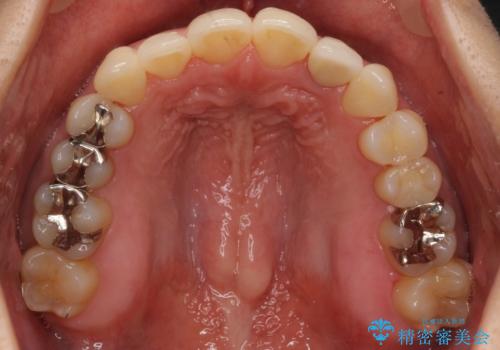

埋まっている奥歯を引っ張り出す インビザライン矯正

埋まっていた歯をしっかり引っ張り出すことができ、また、前歯の見た目も非常に良くなりました。

ワイヤー矯正を奥歯の部分的に行なっただけで、治療の大半をマウスピース矯正で行うことができ、非常に喜んでいただきました。

また、左上の変色した前歯はセラミックでやりかえを行なっています。